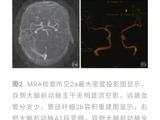

入院体格检查:体重4.3kg,头围36cm,身长52cm,神志清楚,精神差,易激惹,面容正常,前囟平软,心、肺、腹查体未见异常,注视不良,听反应迟钝,颈软,四肢肌张力增高,双侧膝腱、跟腱反射活跃,双跖反射伸性,拥抱及握持反射(-)。辅助检查:电解质、血气分析正常,肝、肾功能正常,4次血乳酸6.19-3.18(正常0.5-2.2)mmol/L,血氨正常;染色体46、XX;血串联质谱分析(MS/MS)及尿气相色谱.质谱分析(GC/MS)未见特异性异常;氨基酸分析正常。脑脊液:外观清,压力50mmH2O(1mmH2O=0.0098kPa),细胞及生化常规正常,乳酸1.54mmol/L。心电图、胸部x线片及腹部B超正常;脑电图:背景2-4Hz δ、θ波,双侧额、中央区棘波、尖波、尖-慢波;头颅磁共振成像(MRI)显示双侧丘脑、基底节区、脑干及双侧小脑、大脑半球白质区片状稍长T1、长T2信号影,于弥散加权(DWI)序列呈高信号(图2);视觉诱发电位(VEP)双侧视P100未引出,脑干听觉诱发电位(BAEP)示右侧外周段异常、左侧脑干段异常,四肢神经电图、肌电图未见异常。

入院后予口服硫胺素(维生素B1)6mg/(kg·d)及左卡尼汀、辅酶Q10等,静脉滴注能量合剂、银杏叶提取物注射液(商品名:金纳多)及脱水剂,维持内环境稳定,治疗第3天患儿易激惹状态好转,哭闹减少,吃奶、睡眠逐渐恢复正常,住院10d复查头颅MRI显示双侧基底节区软化灶,其余异常信号范围略缩小(图2),住院12d出院。出院后基因检查回报,发现患儿SLC19A3基因纯合变异:chr2:228566898(c.137T>C,p.Leu46Pro),为错义变异,其父母该位点均为杂合子(图3),该变异可能导致THTR2蛋白质功能受到影响,其致病性尚未见文献报道[参考数据库:人类基因突变数据库(HGMDPro)及PubMed];线粒体基因检测未见异常。据基因结果及临床表型确诊生物素-硫胺素反应性基底节病(BTRBGD),予口服生物素3mg/(kg·d),硫胺素增至24ms/(kg·d)。患儿3月龄时因痉挛发作半个月再次入院,复查头颅MRI示双基底节软化灶、双侧丘脑区T1稍高信号(图2),复查BAEP正常、VEP双侧P100可引出,复查血乳酸正常,予口服托比酯、静脉滴注甲泼尼龙治疗,痉挛发作逐渐减少,住院2周出院。随诊到4月龄时,痉挛发作停止,患儿吸吮困难、肌张力增高。再次出院后随访半年,精神、运动发育仍落后,无抽搐发作,复查脑电图示背景慢波,可以见到多灶性痫性放电。